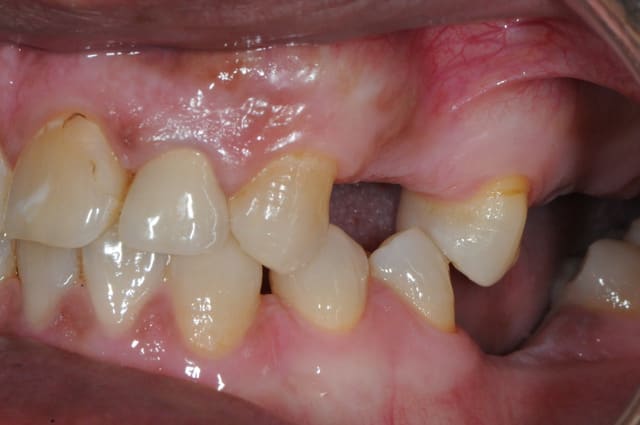

maintenant avec les Léone je fais dans 90% des cas les poses et même les rog en 1 temps chir

"Ma conviction" 25dents suffisent pour un calage

En quoi serait-ce indéfendable? Ca l'aurait été si tu avais fait un bridge ou un stellite.

Ca le sera aussi si tu ne refais pas le compo (inlay?) sur la 5! LOL

dis moi la tu le trouves comment mon compromis avec l'espace biologique

eii

d'après toi faites il y a combien de temps?

Superbe ratrapage suite à une operculisation d'une vis de couverture. Félicitations. Je te savais costaud béotien mais là tu m'impressionnes vraiment.

- pas de vis de couverture , pas d'operculisation!!

Même pas de lambeau pédiculé palatin!

Wouaww les photos beotien !! Quel progrès ! Super !

Oui c'est bon l'humour en fin de semaine. Content que tu le comprennes.

Félicitations sincères, beau résultat.

Surtout n'arrête pas de mettre des photos!